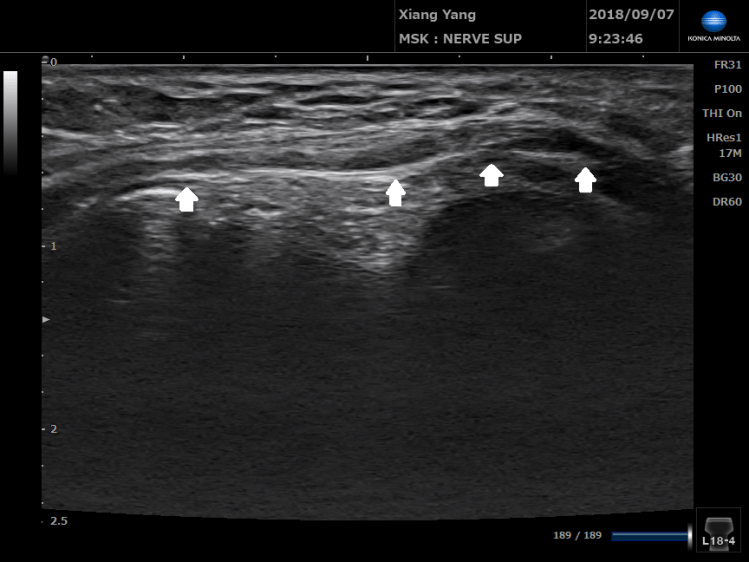

把探頭放在肘隧道處,可以看到手肘伸直的時候,滑車上肘肌用力,把尺神經往內上髁的位置擠出去。 這個就是傳說中的尺神經脫位喔!!